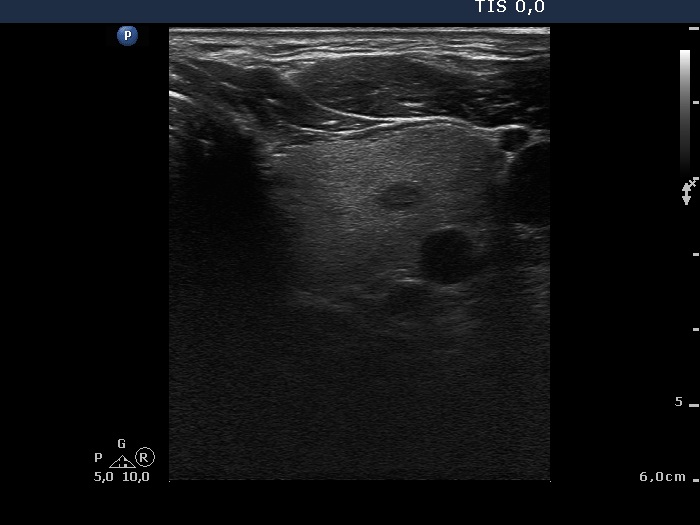

Ultrasonography: The thyroid was echonormal with a few insignificant lesions. There was a large cystic lesion dorsal to the lower third of the right lobe.

After aspiration of 10 ml yellow fluid the size of the lesion decreased from 35x31x42 mm to 29x22x39 mm. The patient refused to aspirate more fluid because her complaints ended.